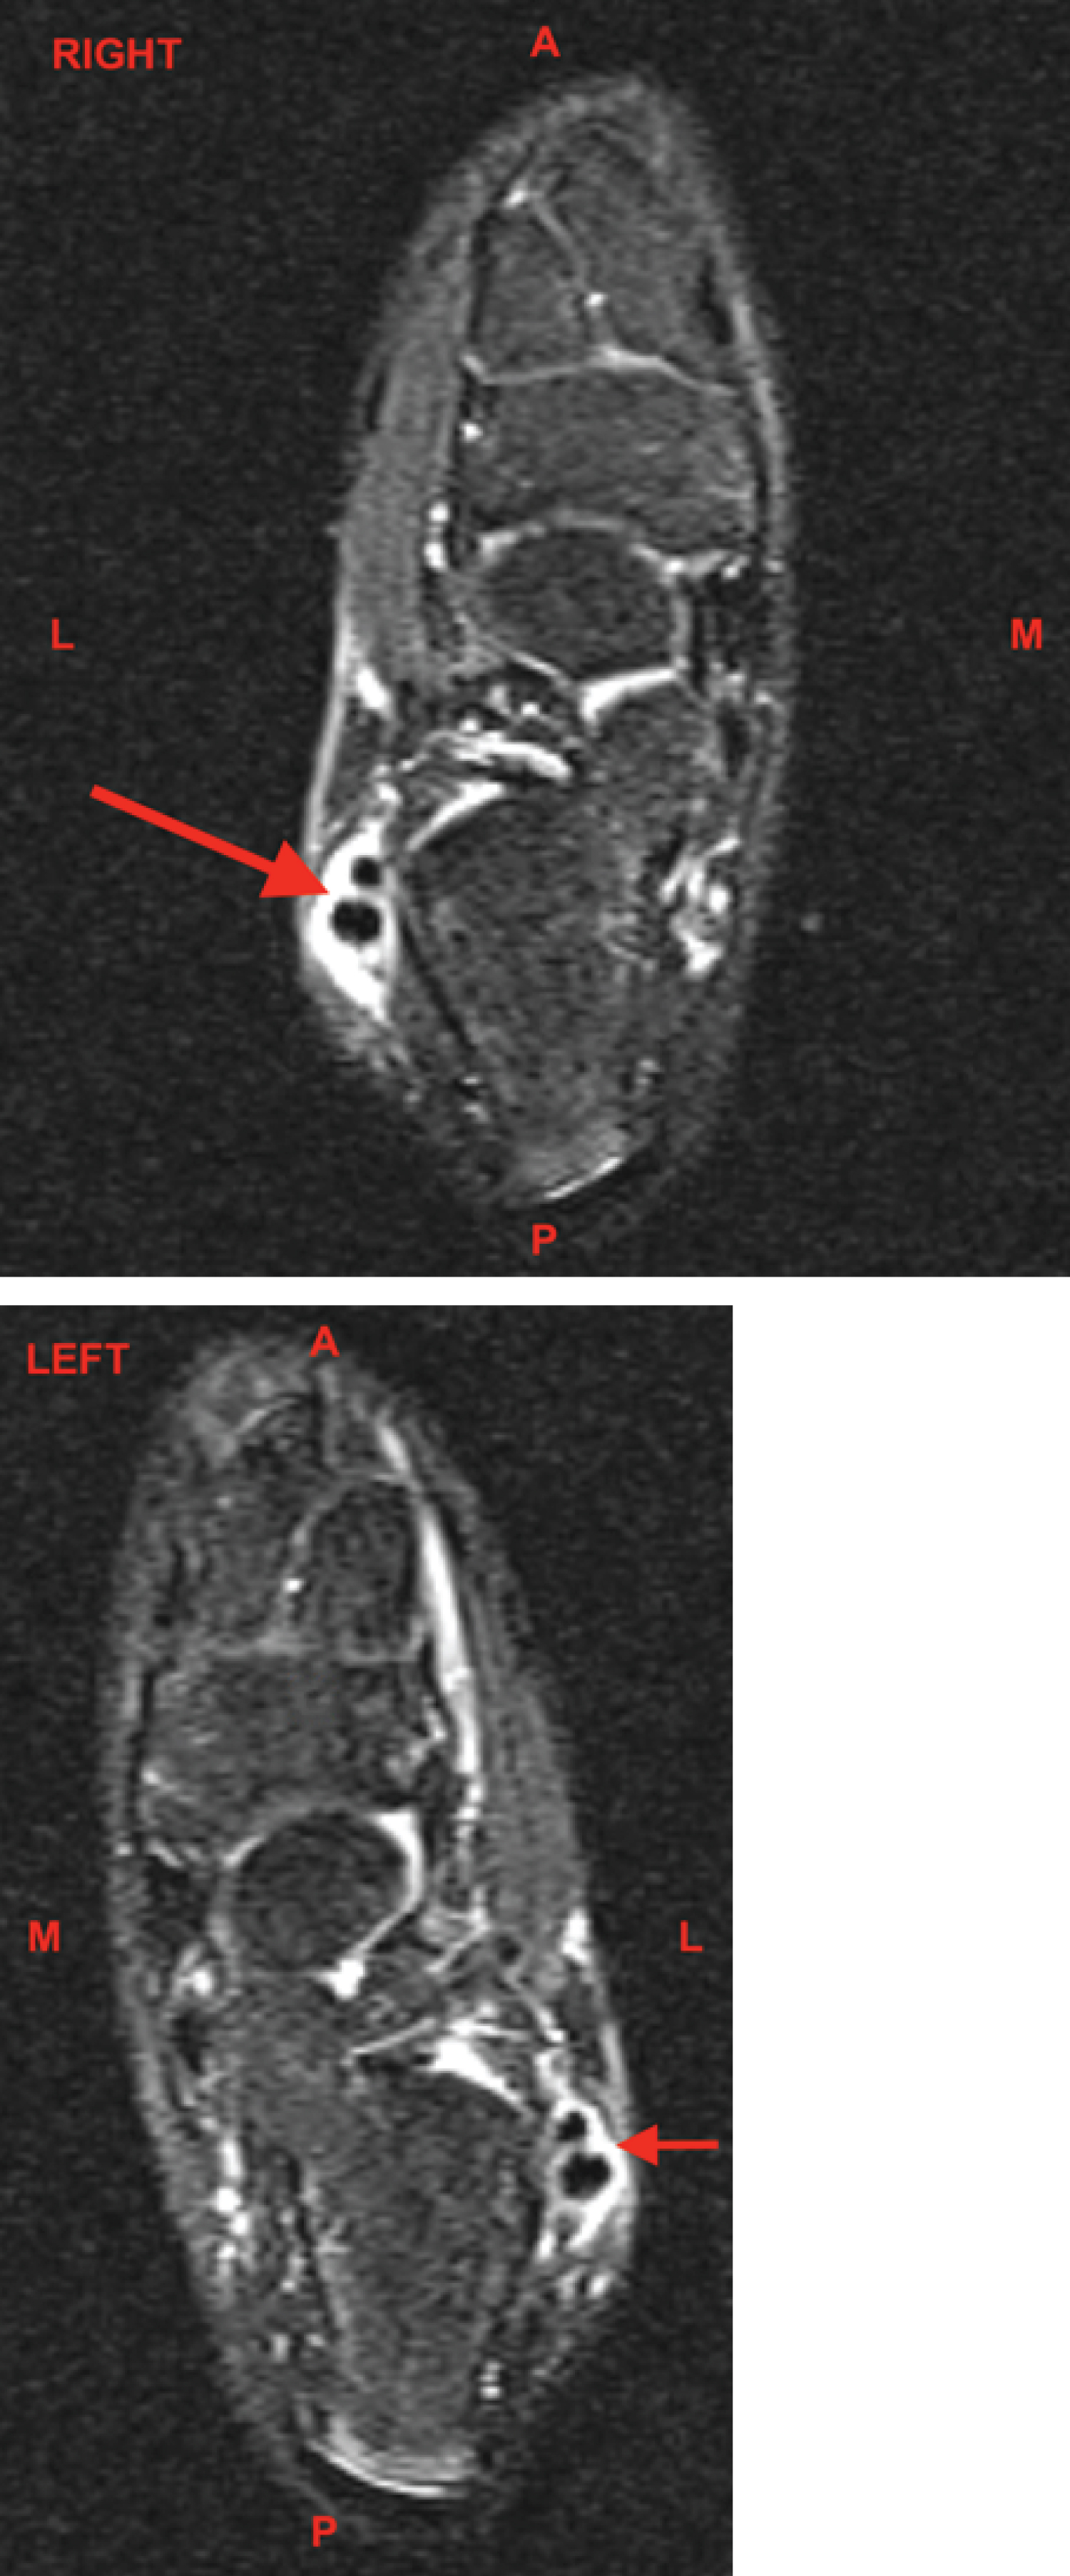

Figures 3 and Figure 4: MRI Ankle, Bilateral, Sagittal, T2 Fat Suppressed without contrast. The red arrows demonstrate the large amount of fluid signal intensity about the peroneus longus and brevis tendons indicative of tenosynovitis. A: Anterior; P: Posterior; M: Medial; L: Lateral View Figure 3 & 4

The patient was placed in bilateral controlled ankle movement (CAM) walker boots and ankle MRIs were completed 10 days after orthopedic consultation. The ankle MRIs were nearly identical bilaterally. Both demonstrated moderate to large amounts of fluid signal intensity around the peroneus longus and brevis tendons compatible with tenosynovitis. Minimal peroneus longus tendinosis was seen at the distal margin of the lateral malleolus bilaterally. Bone marrow edema was seen within the lateral distal aspect of the lateral malleolus, reactive from the peroneal tendon pathology. Soft tissue edema was seen surrounding the area. No injuries were seen to the articular cartilage. The extensor tendons, tibialis posterior, flexor digitorum longus (FDL), flexor hallicus longus (FHL), and Achilles tendon appeared intact. The anterior and posterior tibiofibular, talofibular, calcaneofibular, and deltoid ligaments appeared intact (Figure 3 and Figure 4).